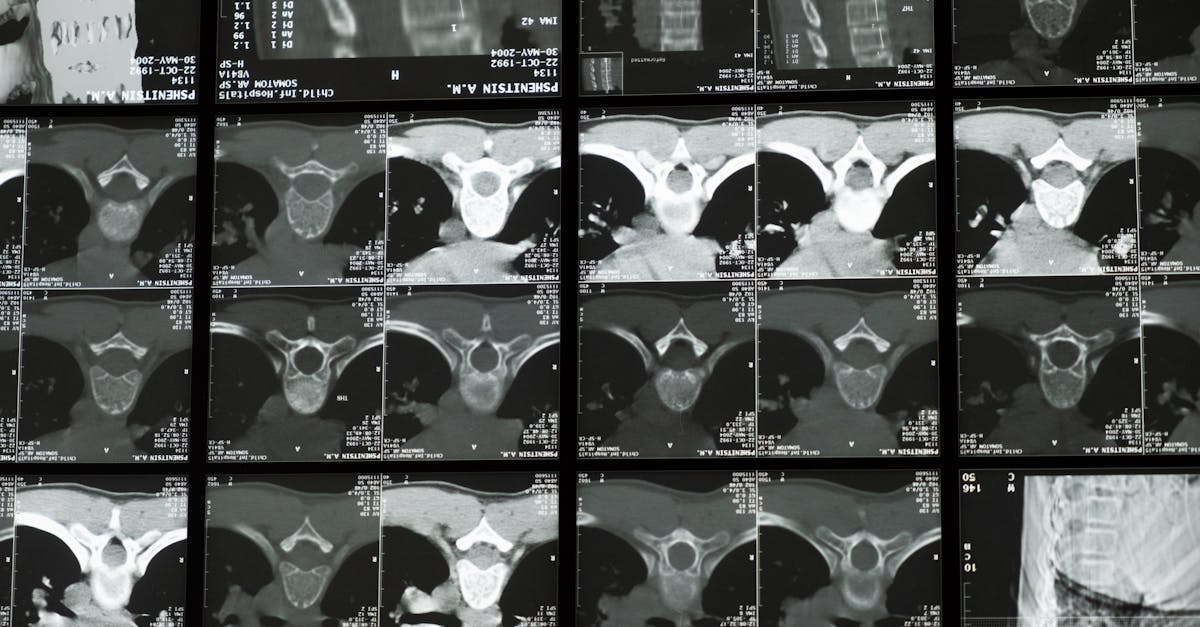

Scoliosis, a condition characterized by an abnormal curvature of the spine, requires a multifaceted approach to treatment. With the advent of high-tech options, patients now have access to innovative methodologies that not only promise effectiveness but also cater to individual needs. This article explores the beneficial impact of emerging technologies and evidence-based practices in managing scoliosis.

One of the most breakthrough advancements in treating scoliosis is the introduction of non-fusion surgical methods. These techniques retain the patient’s natural spinal flexibility while addressing curvature issues. For instance, the ApiFix system is a notable example, utilizing a self-adjusting rod implanted through a posterior approach. This method dramatically reduces recovery times and long-term complications associated with traditional fusion surgeries.

New bracing technologies, such as the ScoliBrace, leverage 3D scanning technology to provide custom-fit solutions for individuals struggling with scoliosis. These braces not only enhance comfort but also ensure a more effective alignment during growth phases. Moreover, recent market entries like SpineCor and WRC focus on ergonomic design and superior functionality, offering a promising alternative for patients of various ages.